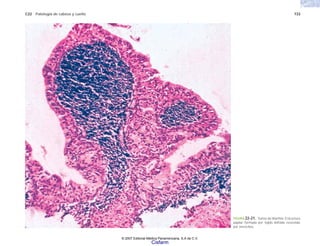

FIGURA 6-13. Granuloma tuberculoso con necrosis central rodeada de células epiteloides en empalizada y células gigantes multinucleadas.

© 2007 Editorial Médica Panamericana, S.A de C.V.